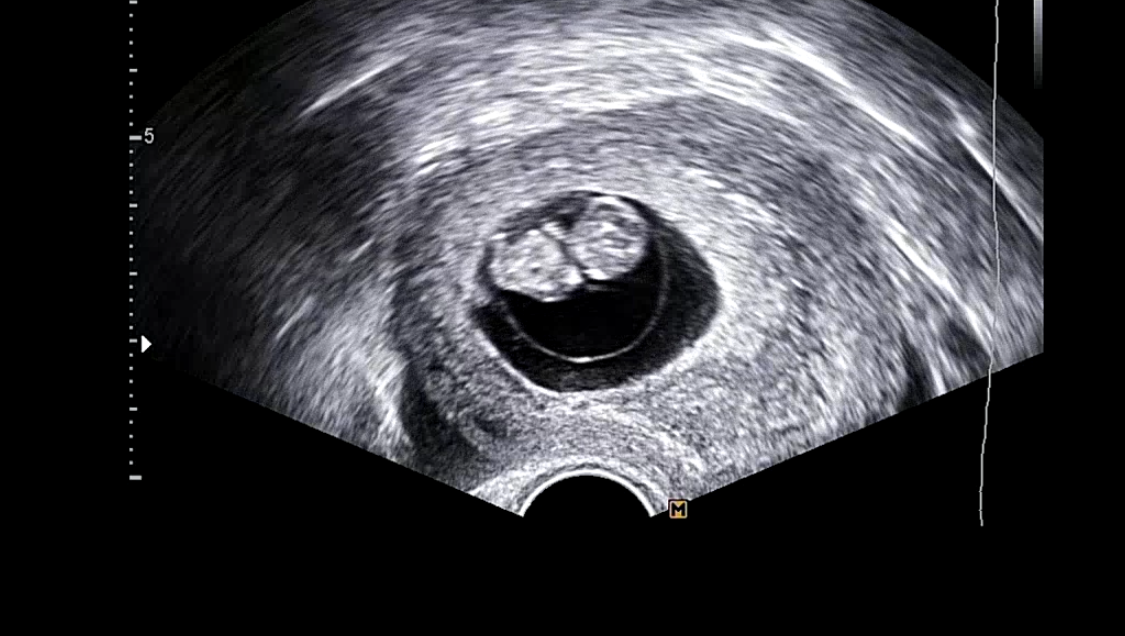

네가 엄마 뱃속에 정말 점으로 있었던 그때부터 말야.

출처: 엄마뱃속